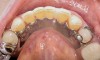

Figure 10  Patient who takes oral bisphosphonates and suffers from periodontal disease.

Figure 10

Figure 11  The radiograph shows 80% bone loss.

Figure 11

Figure 10 shows a periodontal patient who was taking oral bisphosphonates for osteoporosis. The patient had full-mouth scaling and root planing, then was given 2 months to heal and instructed to rinse with chlorhexidine twice daily. After no signs of BRONJ were observed, the patient had full-mouth osseous surgery on her few remaining teeth in the mandible. The surgery was performed all at once and not according to the sextant approach because the patient was on a heart and lung transplant list and was moved up the list while healing from the scaling and root planing. The patient also had extensive bone loss in her anterior mandible (Figure 11). To avoid performing extractions, a simple composite splint was placed between the partial dentures (Figure 12 and Figure 13). The splint reduced the mobility of the teeth and made them less likely to be knocked out during any surgical intubation procedure.